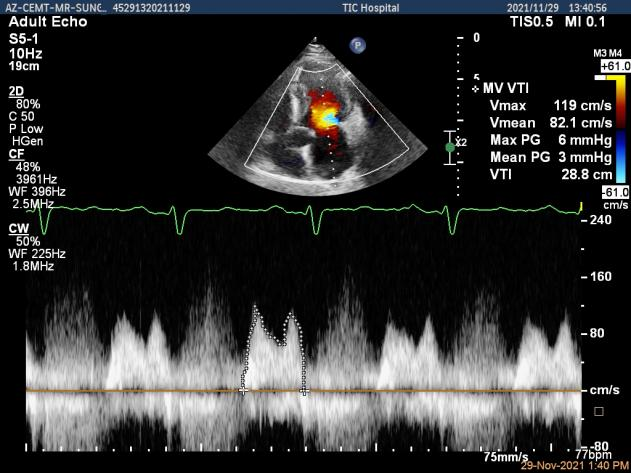

术前超声评估结果

3D-color MV view:大量反流,起源于1区

二尖瓣口平均跨瓣压差:2mmHg

肺静脉血流频谱恢复正向